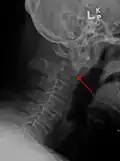

Type 2 dens fracture